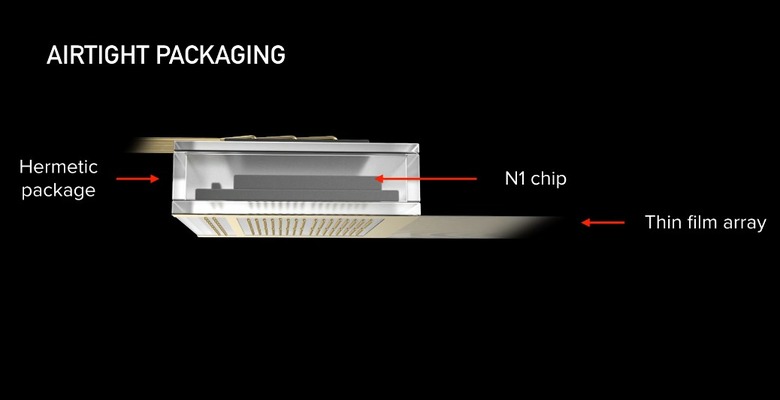

According to the article, its bundles of flexible threads are about one quarter the diameter of a human hair, implanted using needles to avoid blood vessels on the brain's surface. Then the embedded sensors capture information and send it to a receiver (the chip above) on the surface of the skull. From there it transmits wirelessly — Elon Musk said it could Bluetooth the information to your skull. Right now implantation requires drilling holes, but researchers hope in the future they can use lasers to avoid "unpleasant" vibration.

According to Musk, its current v1 4x4mm chip is capable of 10,000 electrodes with "read and write" capability, which he says is more than 1,000 times the number of the best deep brain interface currently available for Parkinson's treatment.